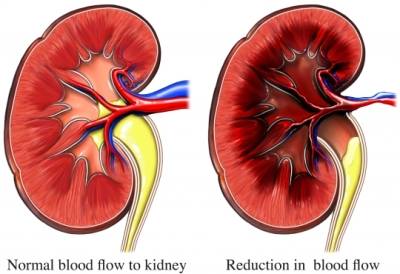

در هر ساعت کلیه های بدن انسان حدود ۷ لیتر مایع را از خون جدا می کنند این مایع را تصفیه کرده و مواد مفید و سودمند آن را به خون بازمی گردانند و مواد مضر آن را از راه میزنای به مثانه می فرستد تا دفع شوند. کجای بدنتان درد می کند مراجعه کنید آیا کلیه تان درد می کند درد کلیه در اثر عفونت کلیه یا آسیب رسیدن به آن ایجاد می شود. اما کار و وظیفه کلیه ها در بدن چیست بیا یاد بگیریم. زمانیکه کلیه ها بدرستی فعالیت کنند مواد زائد از بدن داخل ادرار ترشح می شوند همچنین کلیه ها در تنظیم سایر مواد معدنی در بدن مانند.

کلسیم و فسفر که برای تشکلی استخوان لازمند کمک می کنند مواد. کلیه ها با تولید ادارد در دفع مواد زاید تعادل الکترولیتی تنظیم هورمونی تنظیم فشار خون و هوموستازگلوکز نقش دارند. آناتومی کلیه انسان در بدن انسان به این شکل است که کلیه ها دو عضو لوبیایی شکل در دستگاه ادراری بوده و به دفع مواد زائد به صورت ادرار کمک می کنند. یکی از مهم ترین وظایفی که کلیه ها در بدن بر عهده دارند پاک کردن و تصفیه خون از زباله هاست.